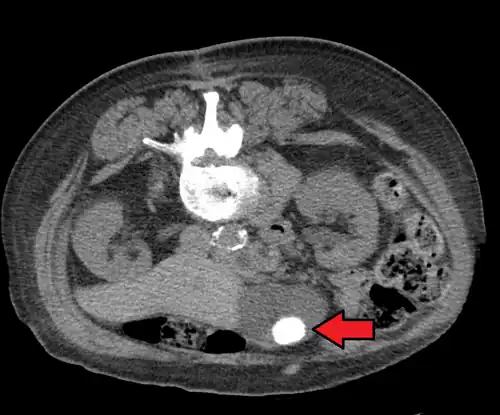

Large gallstone as seen on CT -

CT images of gallstones